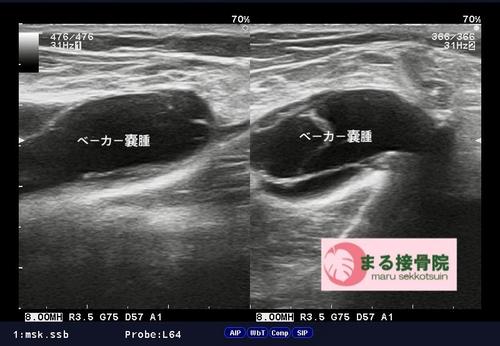

「突然、膝の裏がコブ状に腫れてきた・・・」と御来院。

いつものようにしっかり視診、触診を行い、エコー検査。

結果「ベーカー嚢腫」という症状と判明。

ベーカー嚢腫1.JPG